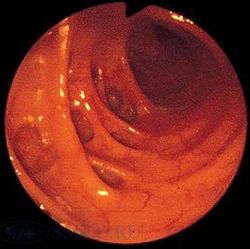

Колоноскопия является основным методом диагностики дивертикулита. Данное исследование позволяет провести дифференциальную диагностику заболевания с неспецифическим язвенным колитом, запорами, кишечной непроходимостью и опухолью толстого кишечника. Во время эндоскопии толстого кишечника при дивертикулите обнаруживаются поврежденные устья дивертикулов с воспалением слизистой оболочки вокруг них. Исследование дает возможность уточнить локализацию кровоточащих участков и оценить интенсивность кровотечения.

- Кишечная эндоскопия. Использование эндоскопических методов диагностики (колоноскопия, ректороманоскопия) показано только после купирования признаков воспаления. Колоноскопия является незаменимым методом поиска источника кровотечения, однако может способствовать появлению осложнений заболевания. Преимуществом эндоскопических методик является возможность проведения биопсии, морфологического исследования биоптатов.

Колоноскопия:

Методом позволяющим визуализировать дивертикулы и выявить осложнения является колоноскопия. При данной процедуре с достаточной достоверностью можно диагностировать воспалительные изменения в области устья дивертикула и выявить кровотечение из дивертикула.